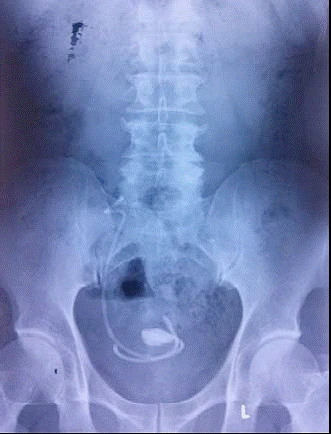

Ống nhựa y khoa nằm trong người người bệnh hằng chục năm, bị bám sỏi, nhiễm trùng.

Trong đó, thời gian bỏ quên “vật lạ” trung bình là 1,63 năm (có trường hợp bị bỏ quên ống này trong người suốt 8 năm), 9/24 trường hợp không biết sự tồn tại ống này trong cơ thể, 20/24 có sỏi bám ống thông, 8/14 bị nhiễm khuẩn đường tiết niệu, 6/24 biến chứng gãy ống thông… Dù các bác sĩ đã rút ống thông thành công nhưng có người bị choáng nhiễm trùng và đã tử vong.